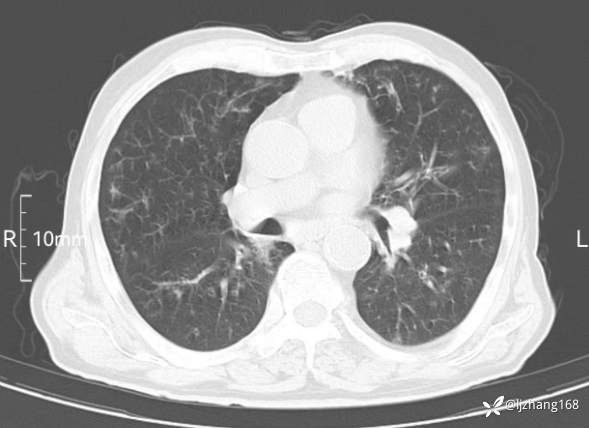

老年男患,咳嗽,气短,双肺多发间质性病变,何种感染?(有结果)

辅助检查:胸部CT:双肺肺气肿,间质性病变,血气分析:PH 7.413, PCO2 29.2mmHg, PO2,81.8mmHg,乳酸 3.3mmol/1,剩余碱-4.0mmol/1,HC03 18.8mmol/1。全血超敏C反应蛋白:超敏C反应蛋白 135.60 mg/L、 白细胞 14x19^9/L,中性粒细胞11.6x10^9/L。